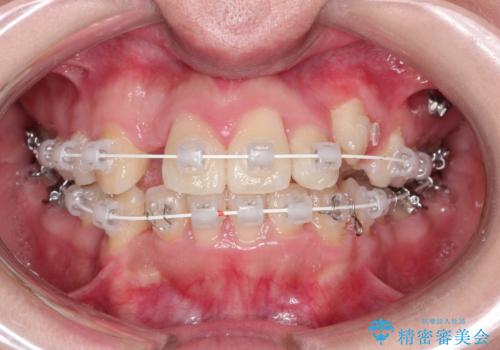

犬歯が変な位置にある 抜歯矯正により正しい位置へ

左上の犬歯が通常の位置より、かなり上方にあり、乳歯の残存と前歯のがたつきがありました。

残った乳歯と上下左右の永久歯を1本ずつ抜歯して、ワイヤーにて矯正することとしました。

犬歯も通常の位置にまで移動することができ、口元もすっきりすることができました。